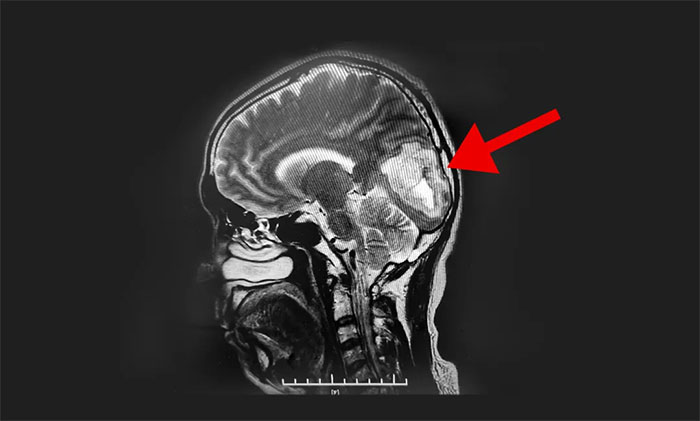

頭顱MRI平掃+增強提示:左側(cè)枕葉占位性病變。根據(jù)患者影像學(xué)檢查,李士其教授、潘仁龍主任、吳治群博士會診認(rèn)為膠質(zhì)瘤可能性大,并造成患者生活質(zhì)量下降,應(yīng)盡快行手術(shù)治療,明確病理診斷。

▲ MR顯示腫瘤超5厘米大小

經(jīng)過充分術(shù)前準(zhǔn)備后,8月23日,李士其教授在吳治群博士、黃秀夫醫(yī)生協(xié)助下為患者進(jìn)行了左側(cè)枕葉腫瘤切除術(shù)。顯微鏡下,李士其教授根據(jù)定位,于左側(cè)枕葉腦組織表面切開,游離腦組織,見深處有暗紅色腫物,考慮為腫瘤,腫瘤質(zhì)軟,呈實性,血供豐富,自四周分離腦組織與腫瘤,并切除腫瘤,向右切除至大腦鐮,向下、向深處切除至小腦幕,向上、向左側(cè)切除至腫瘤邊界外,在充分保護神經(jīng)功能的前提下,歷時約五小時,最終5公分大的腫瘤被順利切除。